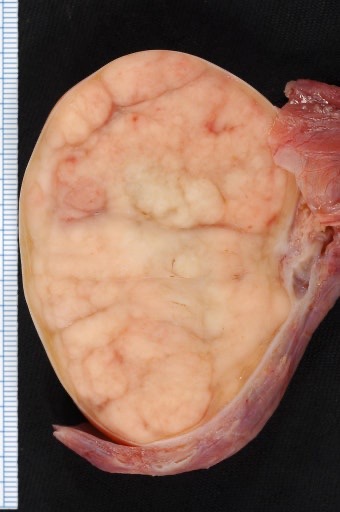

고환암은 남성 생식기관인 고환에 발생하는 악성 종양으로, 초기에는 대부분 통증이 없는 것이 특징입니다. 가장 흔히 보고되는 증상은 한쪽 고환에 단단하게 만져지는 결절(혹)이나 덩어리가 느껴진다는 점입니다. 이런 덩어리는 대체로 시간이 흐르면서 점차적으로 커지는 경향이 있으며, 만졌을 때 통증 없이 딱딱하고 경계가 뚜렷한 특징을 보입니다.

또한 고환의 질감 변화 역시 중요한 신호입니다. 원래는 부드럽고 탄력 있는 조직이던 고환이 암의 진행에 따라 전체적으로 단단하게 느껴질 수 있습니다. 자가검진을 통해 평소와 달리 단단해졌음을 느꼈다면 병원을 방문할 필요가 있습니다.